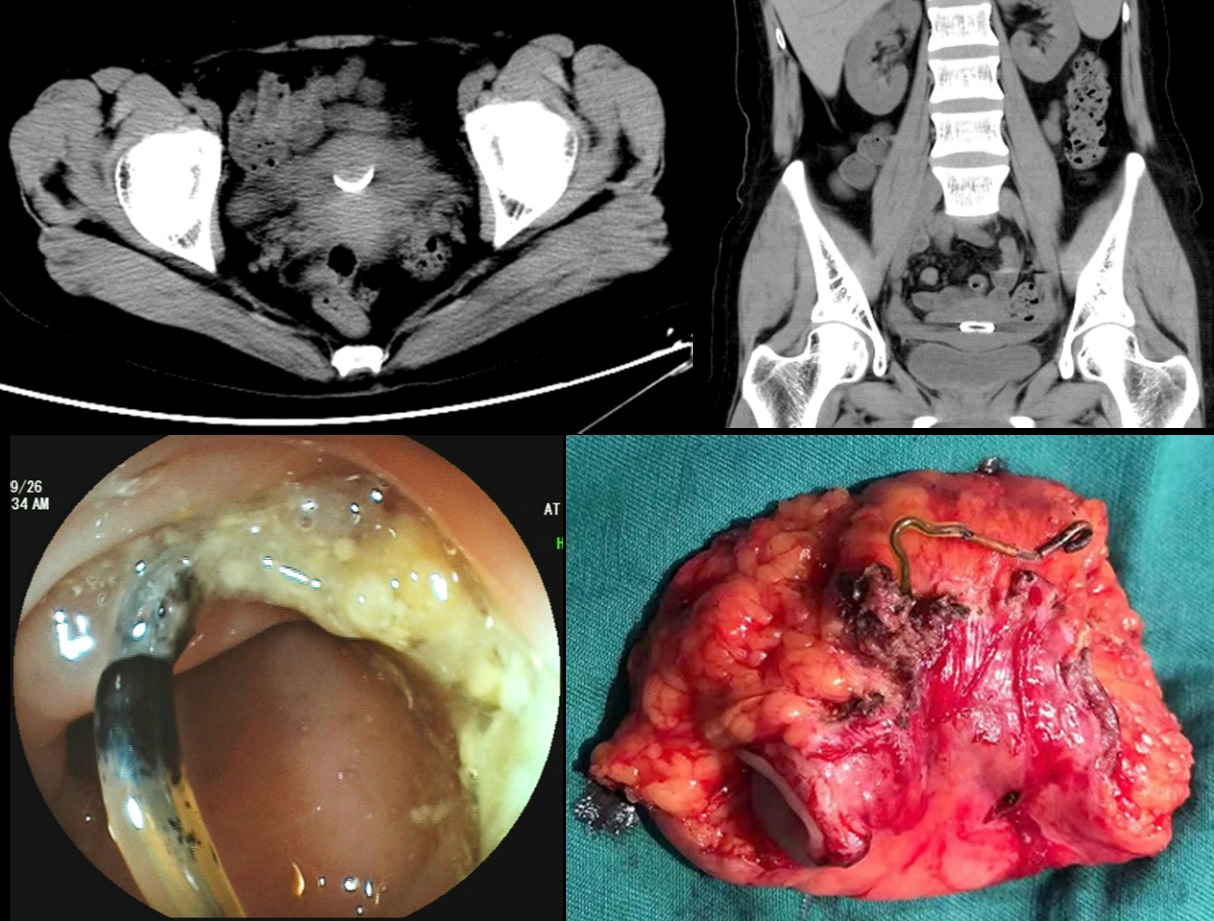

A 38-year-old woman was transferred to our hospital with a 10-day history of lower abdominal pain and vomiting. She had no significant surgical and medical history. Physical examination showed no specific abnormality. Computed tomography of the abdomen and pelvic cavity incidentally showed a thin, irregular foreign object embedded in the right lateral wall of the rectum (Figure 1A and 1B). Colonoscopy confirmed perforation of the rectum by a thin metallic object (Figure 1C). On detailed questioning, she recalled having an intrauterine device inserted 9 years ago. The patient received the diagnosis of rectal perforation by an intrauterine device. The device was successfully removed laparoscopically by performing a partial rectectomy (Figure 1D). The postsurgical course was uneventful and she became asymptomatic after the procedure. As a safe and effective birth control method, insertion of intrauterine contraceptive device is very popular in China. However, the migrated device may present as bleeding, abdominal pain, and even colonic perforation although most of the perforations are asymptomatic [1]. Migrating intrauterine contraceptive devices are usually involved in the sigmoid colon, which is the most commonly penetrated part of the colorectum [2]. As a rare complication of intrauterine device insertions, Uterine perforation may subsequently result in rectal perforation in our case. Minimally invasive techniques such as colonoscopy and laparoscopy are usually performed to remove the device eroding the colon wall [3].

Figure 1: Rectum Penetration by an Intrauterine Device. (A,B). Computed tomography showing a thin, irregular foreign object embedded in the wall of the rectum. (C). Colonoscopy view showing the device clearly penetrating the rectal wall. (D). The device was successfully removed laparoscopically.